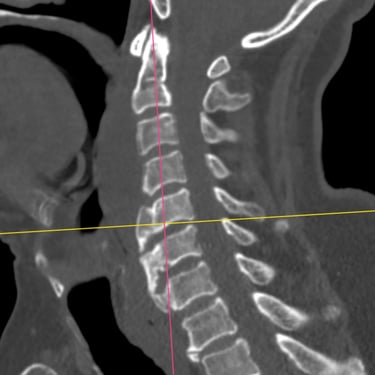

Discitis Cervical con Absceso: Descompresión Cervical y Artrodesis

La discitis cervical con absceso es una infección grave de la columna que puede comprometer el disco intervertebral, los cuerpos vertebrales y las estructuras neurológicas, generando dolor cervical intenso, fiebre y déficit neurológico progresivo. Cuando existe compresión medular o inestabilidad, el tratamiento quirúrgico mediante descompresión cervical y artrodesis es fundamental. Este procedimiento permite drenar el absceso, liberar la médula espinal y estabilizar el segmento afectado, favoreciendo el control de la infección y la recuperación neurológica. El manejo oportuno y multidisciplinario es clave para mejorar el pronóstico del paciente.